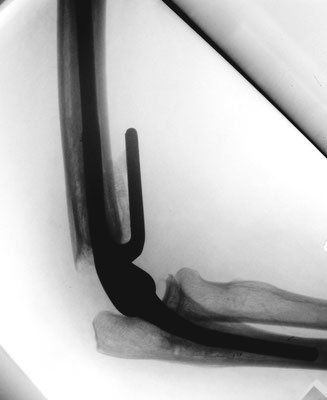

Ellenbogennaher Oberarmbruch/suprakondyläre Oberarmfraktur

Diese Brüche gehen häufig mit einer erheblichen Zertrümmerung des Knochens einher. In den meisten Fällen ist auch die Gelenkfläche betroffen, so dass eine operative Rekonstruktion erforderlich ist. Wie bei allen gelenknahen Knochenbrüchen besteht die Aufgabe darin, ein sehr kurzes Knochenfragment an dem Schaftknochen zu befestigen und die Gelenkfläche stufenlos wieder herzustellen. In der Standardtechnik werden dabei zwei Platten benutzt. Dabei geben insbesondere die winkelstabilen Titanplatten optimale Möglichkeiten um die kleinen Knochenteile stabil zu befestigen.

Ist allerdings die Gelenkfläche so stark zerstört, dass eine Rekonstruktion nicht möglich ist, bietet sich bei Patienten in höherem Lebensalter die Implantation einer Ellenbogenprothese an. Mit dieser ist eine gute Funktion zu erreichen.